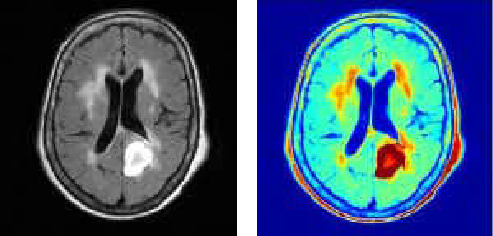

颜色分割可用于检测身体肿瘤、从森林或海洋背景中提取野生动物的图像,或者从单一的背景图像中提取其他彩色物体。下面几幅图是图像分割的几个典型示例。:

医学中的颜色分割